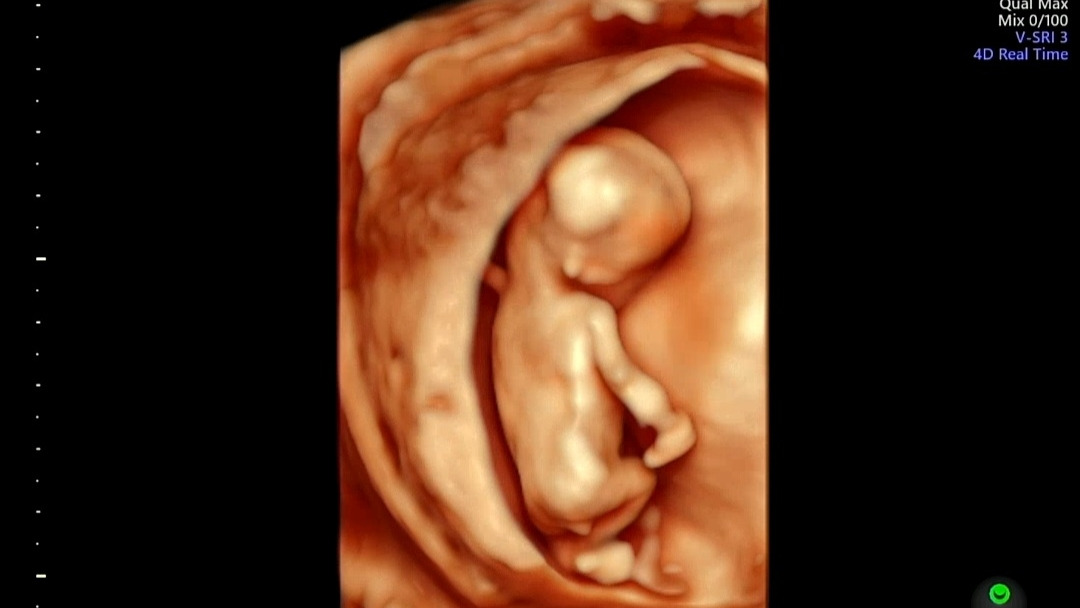

덕순이의 작은 머리

16주 차

의 아기는 존재감을 나타내기엔 아직 너무 작았다.

머리 둘레 12.83cm, 허벅지 뼈 2.09cm, 추정 몸무게 150g...

대충 짐작해도 한 손바닥에 폭 잠길만한 크기였다.